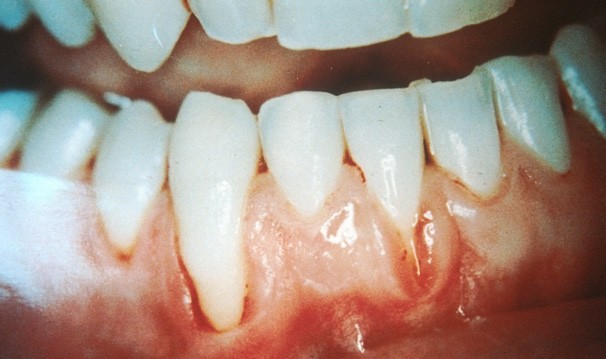

Gum recession is when the margin of the gum tissue surrounding the teeth wears away, or pulls back, exposing more of the tooth, or the tooth's root. When gums recede, gaps can form between the gum and tooth, allowing disease-causing bacteria to build up. If left untreated, the surrounding tissue and bone structures of the teeth can be damaged.

Long Teeth.- One symptom is the visible lengthening of the teeth. When gums recede because of periodontal disease, the teeth have the appearance of being much longer than normal.

Exposed Roots.- Exposed roots are another symptom, and can be extremely sensitive and uncomfortable. They are often a sign of periodontal disease or can be attributed to brushing overly aggressively with a toothbrush with hard bristles.

Loose teeth.- When suffering from receding gums, you may notice loose teeth, attributed to the bacteria and periodontal disease under the gums around the teeth. As receding gums worsen, the gum pockets deepen due to loss of attachment structure.